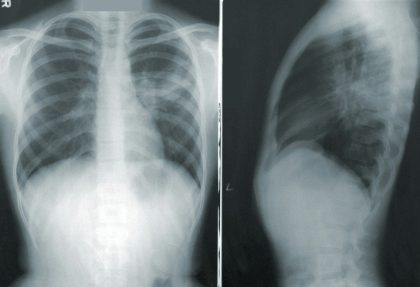

胸部レントゲン:肺炎や影がないかを確認